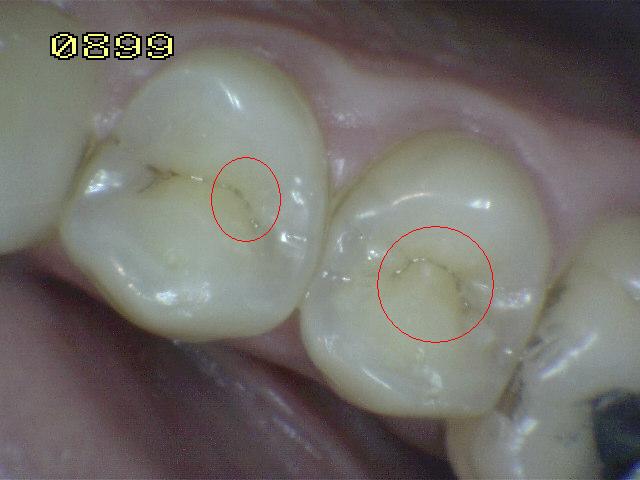

Código 3:

Ruptura localizada del esmalte debido a caries sin dentina visible

- El diente visto en estado

húmedo pueden tener una clara opacidad de caries (lesión de

mancha blanca)

y / o decoloración marrón de caries que es más ancha que la

fisura natural y la fosa, que no es consistente con la

apariencia clínica de esmalte sano. Una vez seco, se

observa una pérdida de estructura dental cariada en la

entrada, o dentro de la fosa o fisura . Esto se ve

visualmente como evidencia de desmineralización en la

entrada o dentro de la fisura o fosa, y aunque la fosa o

fisura puede aparecer sustancialmente más ancha que lo

natural, la dentina no es visible en las paredes o la base

de la cavidad ó discontinuidad .

-

En caso de duda, o

para confirmar la evaluación visual, la sonda de la OMS /

IPC / PSR puede ser

utilizada con cuidado a través de la superficie del diente,

para confirmar la presencia de una cavidad ( < 0,5mm.de

profundidad) al parecer limitada al esmalte . La

identificación de la cavidad se consigue deslizando el

extremo de la bola a lo largo de la fosa o fisura

sospechosa.